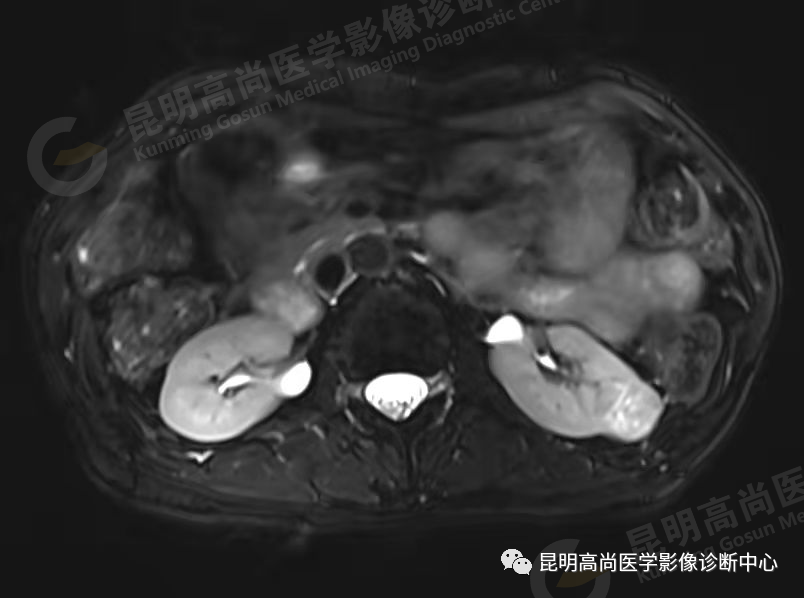

于 2021 年 9 月 9 日在本中心行 MRI 平扫检查;

影像诊断:左肾下份囊实混合性占位(局部可疑脂质成分),性质待定,恶性不能除外,建议进一步增强检查明确。

(3)MRI 检查

一次扫描可获得肾脏横断面、冠状面和矢状面的图像;

没有 CT 图像中存在的伪影;

不需要注射造影剂。MRI 可十分清晰地显示肾实质肿块。肾癌密度高低不等、信号强度不均匀和肿块边界不规则。肾细胞癌的 T1 比正常肾实质的 T1 长,而 T2 相同或稍长。MRI 显示肿瘤侵犯的范围优于 CT,可用于肾脏肿瘤的术前分期和术后随访。